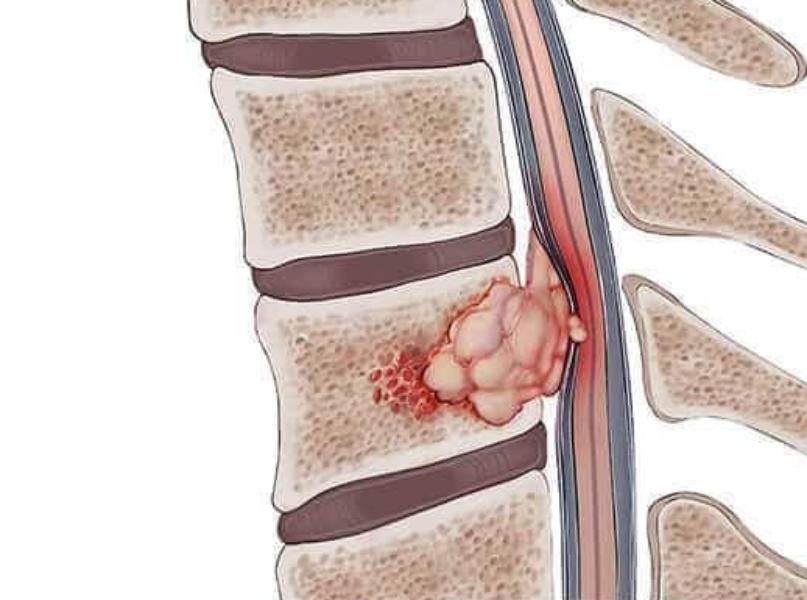

Spine Tumor Treatment in Thane - Specialized Care for Spinal Stability and Nerve Safety